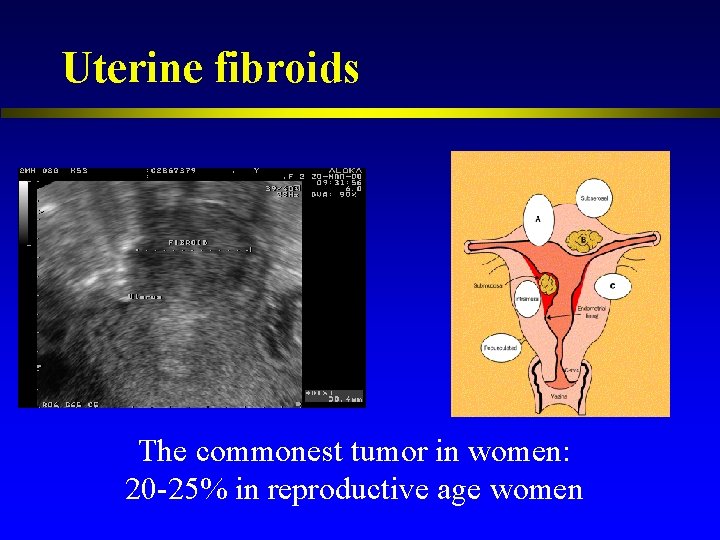

Uterine fibroids The commonest tumor in women: 20 -25% in reproductive age women